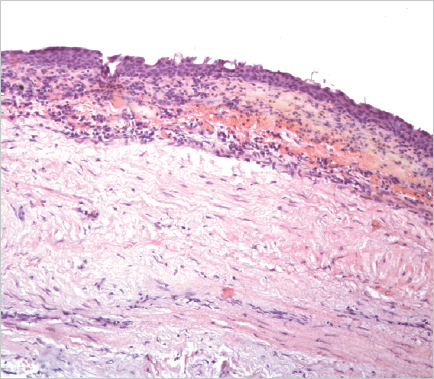

Histological examination of the removed paraurethral cyst was performed (Fig. 6–8).

Fig. 6.The wall of the paraurethral cyst, surgical material. Hematoxylin-eosin staining, ×100. The cyst wall is represented by fibrous tissue with moderate chronic inflammation, fresh hemorrhages (intraoperative) and covered with a transitional epithelium

Рис. 6.Стенка парауретральной кисты, операционный материал. Окраска гематоксилином и эозином, ×100. Стенка кисты представлена фиброзной тканью с умеренно выраженным хроническим воспалением, свежими кровоизлияниями (интраоперационными) и покрыта переходным эпителием